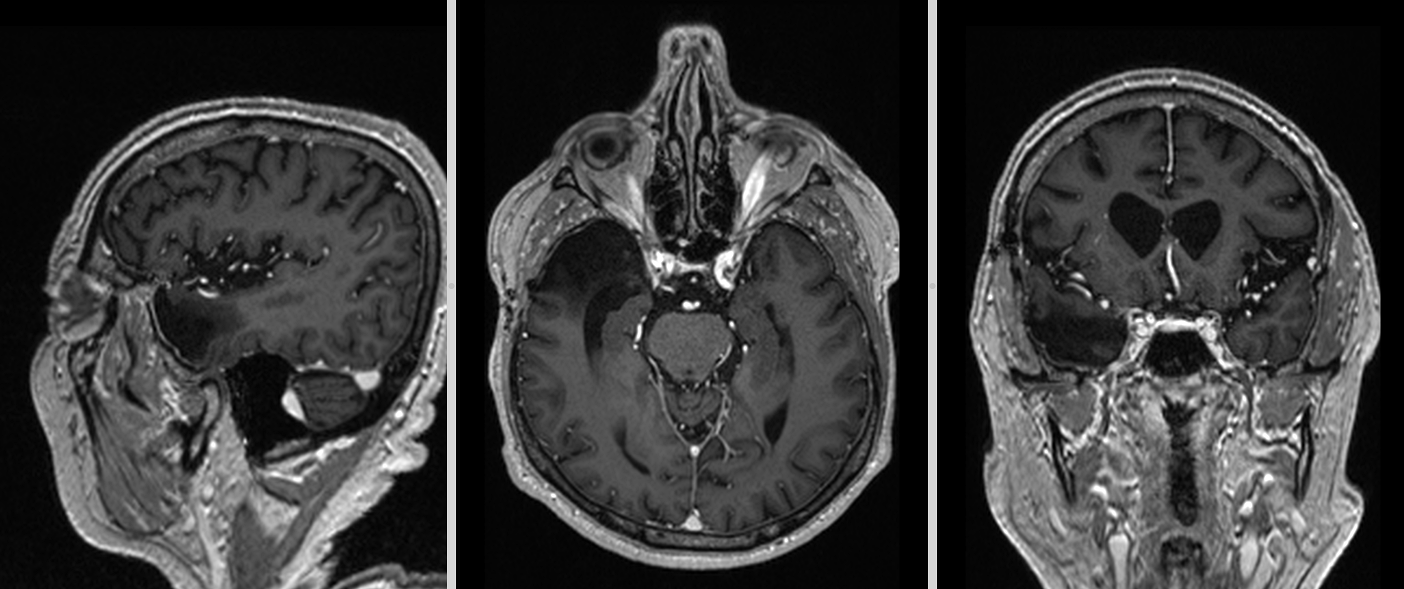

La fel la 5 ani – fără tumoră reziduală sau recurentă. Putem considera că pacientul este vindecat.

RMN postoperator la 5 ani